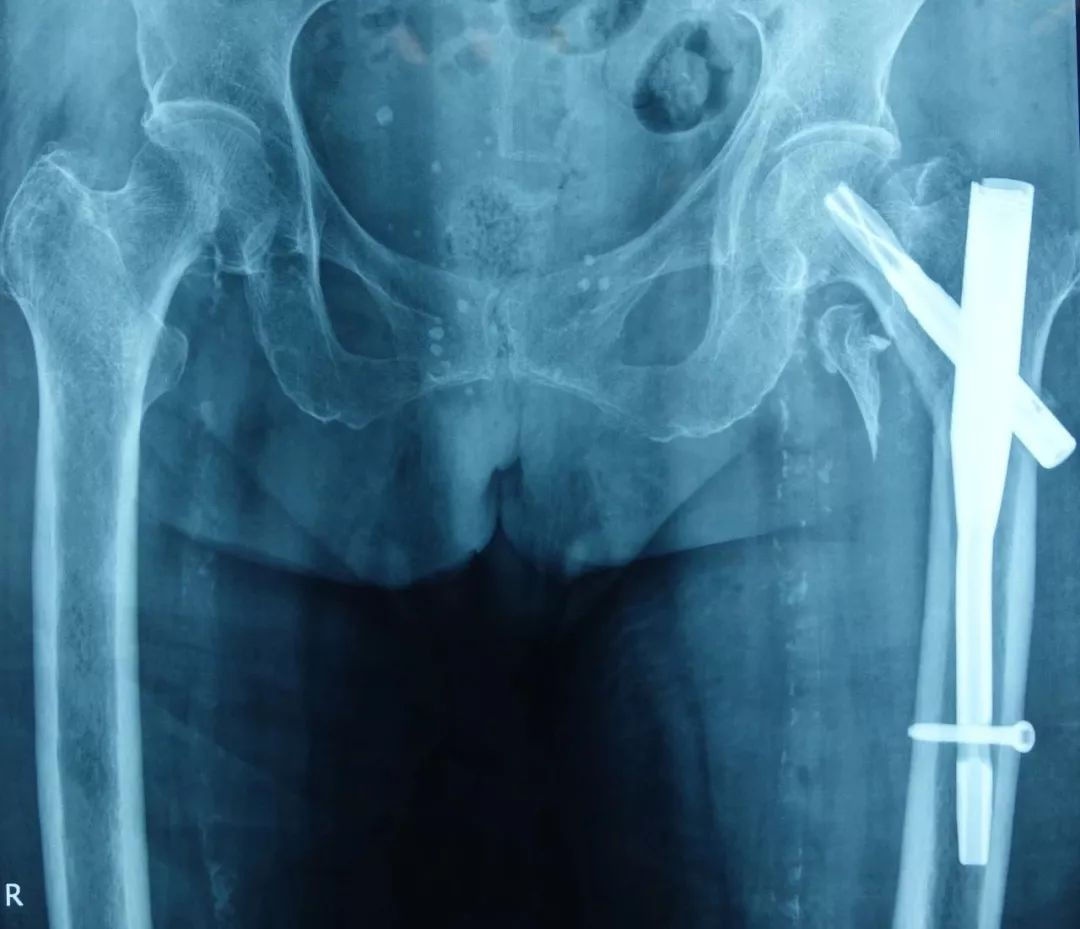

外院医生给这位患者做了骨折内固定手术,可以看到骨折对位良好,骨碎块未作特殊处理。